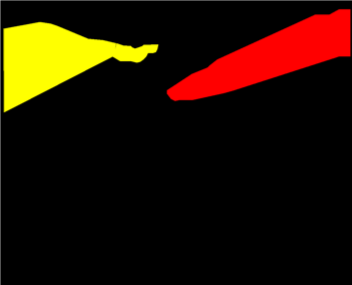

As robotic minimally invasive surgery has developed, with platforms such as da Vinci becoming the de-facto standard-of-care for certain urological, gynecological and general surgical procedures, there has been an increase in focus in how assistive systems based on computer vision and machine learning can improve surgeon performance and patient outcomes. Many potential applications are dependent on scene understanding and for this, accurate segmentation of instruments is an important component. For instance, instrument tracking algorithms which underlie automation and guidance assistance often build upon segmentation [4] or alternatively masking augmented reality overlays of 3D imaging modalities requires pixel labelling of the instruments to prevent their occlusion (see Fig. 1).

Our challenge was made up of 3 sub-problems. The first was binary instrument segmentation, where each frame was separated into da Vinci Xi instruments and a background class, which contained an ultrasound probe, surgical clips and porcine tissues. The second task was instrument part segmentation, where we scored the participants on whether they could correctly segment each articulating part of the instrument (see Fig. 3). Our final task was to segment and classify the instruments (see Fig. 4).